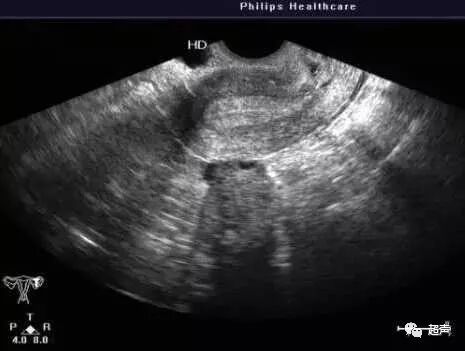

内膜分型是个不断变化的过程,所以各位病友不必太纠结分型。只要知道胚胎移植时内膜的厚度至少能达到7mm,分型可能A或B型会更好一些。还有一种就是月经期来做B超时宫腔内还有积血,所以宫腔会有分离,这时我们报告里会描述宫腔分离多少,单层内膜厚多少。

宫腔分离